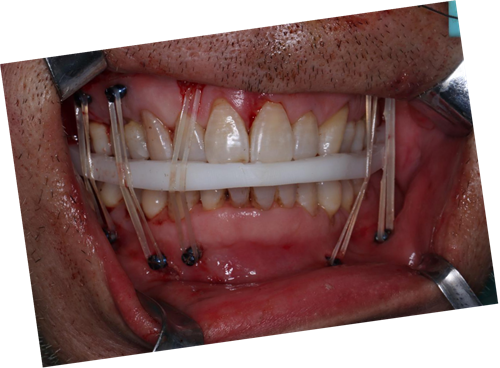

术中咬合板就位